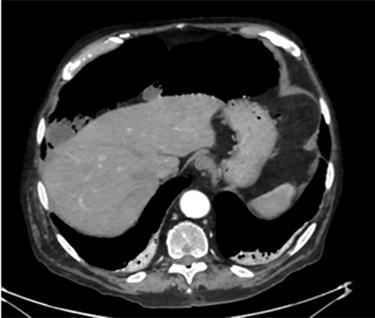

PCI first documented by Du Vernoy in 1783 [4] refers to the intraoperative or radiological findings of intramural gas-filled cysts in the bowel wall (Fig. 4). PCI can easily mimic pneumoperitoneum on radiological imaging as CT, being a very sensitive examination, may show even minimal circumferential gas collections outside the bowel lumen or misrepresent some findings [5]. Liu et al. [6] found that PCI was misdiagnosed as a surgical abdomen in up to 27% of cases resulting in unnecessary operation. It is important to differentiate idiopathic PCI with a secondary form of this condition known as pneumatosis intestinalis which is not in fact a disease but a rare finding characterized by the presence of gas in the submucosal and/or subserosal of the bowel wall that may result from an underlying pathological process (Table 2). PCI has a reported incidence in general population of 0.03% on autopsy series and up to 0.37% in CT series. Its prevalence is still unknown [7]. However, Adachi et al. [8] in a retrospective, single-center study found 24.7% of PCI cases in the selected group affected by pneumoperitoneum. PCI involves most commonly the small and large bowel (respectively 42% and 36% of cases; in 22% is concomitantly present), but could also involve the mesentery and omentum [7]. Physiopathology remains still unclear although some hypotheses have been proposed such as: the ‘mechanical theory’ where an increased pressure of intraluminal gas secondary to mechanical problems breach the mucosal or serosal layers (i.e. blunt trauma, persistent vomiting, ileus or endoscopy); the ‘bacterial theory’ where an excess of intraluminal bacterial production of nitrogen gas diffuse through the bowel wall; the ‘chemical theory’ where malnutrition can prevent the digestion of carbohydrates and increased bacterial fermentation in the intestine; the ‘pulmonary theory’ that refers to increased intraluminal bowel pressure due to the respiratory system [9].

PCI was ultimately identified retrospectively using lung window settings.